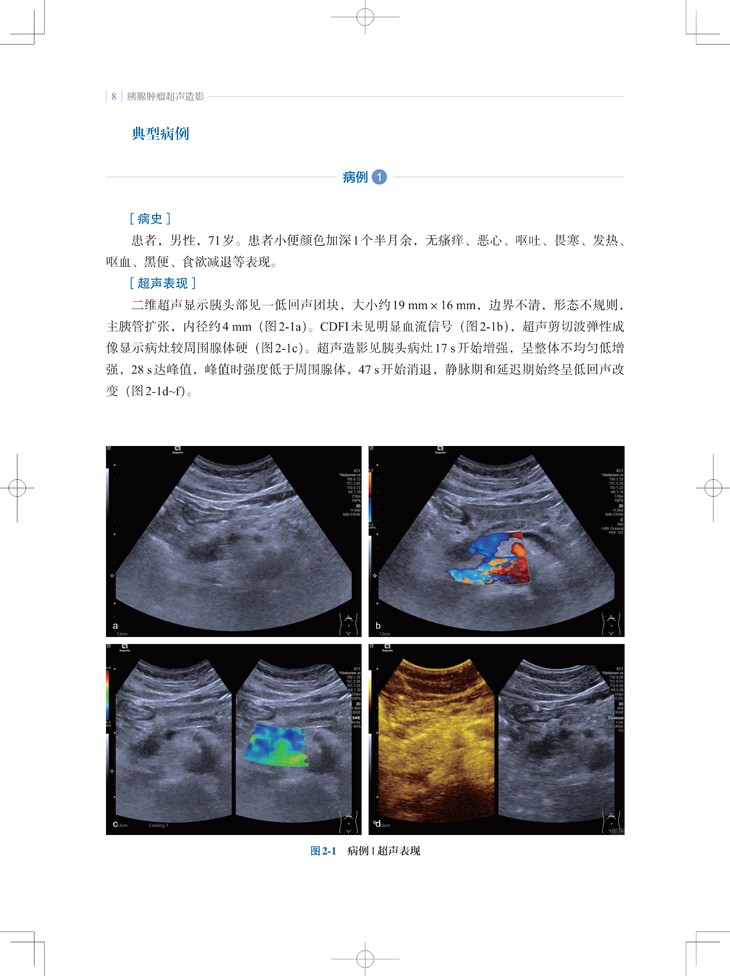

本书是“东方超声文库”系列之一,介绍了超声造影剂和实时超声造影技术在胰腺肿瘤诊疗领域的最新应用。内容包括胰腺肿瘤的超声造影表现特点、诊断要点,超声造影在随访胰腺癌非手术治疗、预测胰腺切除术后并发胰瘘、胰腺癌微创介入治疗中的应用;此外,通过与胰腺肿瘤的CT、MRI等影像学表现的对比,让读者对超声造影检查技术有更全面的认识。

2. 内容实用:超声造影不但提高了胰腺肿瘤定性诊断的准确性,而且能反映胰腺肿瘤微血管的血流动力学改变,本书对从事胰腺肿瘤诊断和治疗的各领域、各级临床医师有实用指导意义。

3. 编写方式契合临床:不仅有胰腺肿瘤造影影像图,还有与CT/MRI等影像学表现的对比及手术照片。